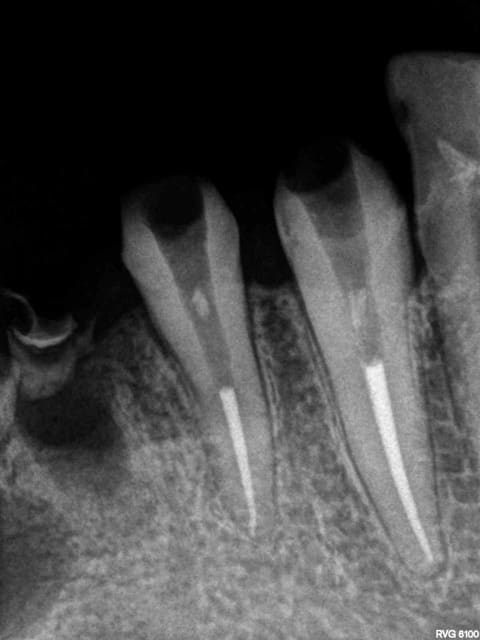

1 rdscif - Eugenol

X ray 03 medium zvq18j - Eugenol